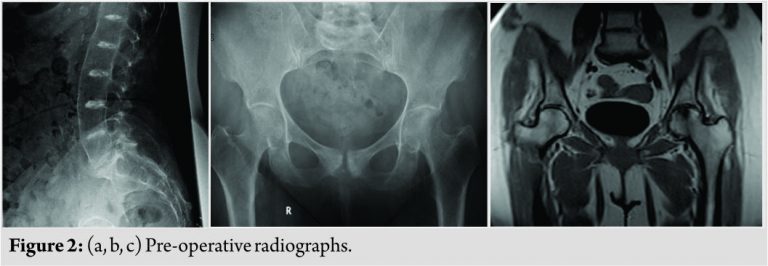

The urinary HGA levels were 11500 mg/24 h (average normal being <10 in our laboratory). Plain radiographs of the hip and lumbar spine revealed significant advanced degenerative changes in both the hips and lumbar spine(Fig. 2a, b, c).

Magnetic resonance imaging of the hips confirmed the same. The authors decided to proceed with a total hip replacement of both her hips. The goal of surgery was to obtain a painless range of motion for both her hips. A staged bilateral total hip replacement surgery was performed9months apart. The anterolateral approach was the preferred approach used by the treating author. Intraoperatively, the head of the femur presented a blackish-brown discoloration, and the surrounding tissues had a brownish tinge to them (Fig. 3).